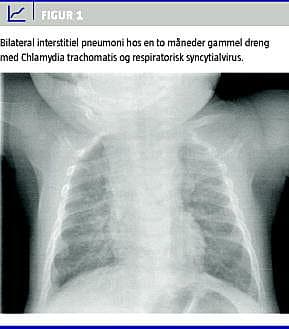

En røntgenundersøgelse af thorax viste bilaterale, diffuse, småplettede infiltrater. Billedet gav mistanke om interstitiel pneumoni (Figur 1 ).